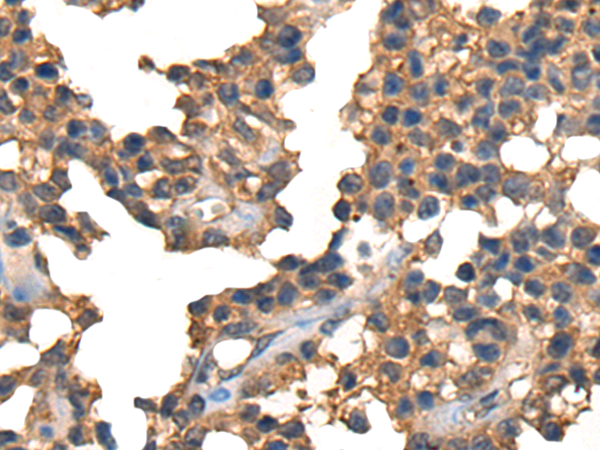

IHC positive control: |

Human liver cancer and Human ovarian cancer |

IHC Recommend dilution: |

25-100 |